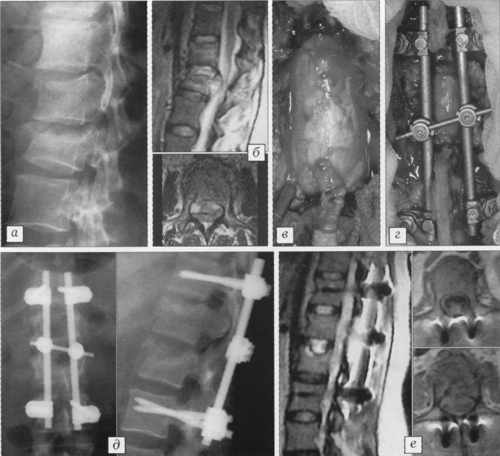

На рис. 2 представлен результат лечения осложненного перелома первого

и второго поясничных позвонков у 37-летней пациентки. Клиническая картина включала

нижнюю параплегию и нарушение функции тазовых органов. Через 16 ч после травмы

больной произведены декомпрессивная ламинэктомия, менингомиелорадикулолиз, репозиция,

восстановление высоты позвонка путем пластики тела аутокостной крошкой через

ножку позвонка и фиксация системой USS. Через 6 нед - полное восстановление,

пациентка вернулась к привычной работе.

Рис. 2. Больная 3. 37 лет.

a - рентгенограмма при поступлении: компрессионный осложненный перелом

L1-2;

б - МРТ при поступлении: компрессия корешков конского хвоста телом L2;

в - декомпрессия дурального мешка;

г - фиксация USS;

д - рентгенограммы после операции;

е - МРТ после операции: полноценная реконструкция позвоночного канала. |